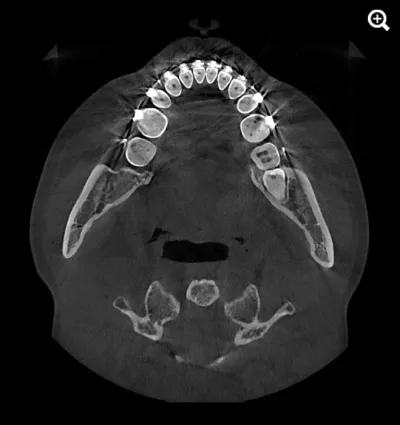

When capturing a CBCT scan, the presence of metal in the oral cavity can introduce artifacts, shadows, and bright streaks that significantly compromise image quality. These distortions may obscure critical anatomical structures, making it more difficult to evaluate bone integrity and surrounding areas—adding complexity to diagnosis and increasing clinical stress.

HDX WILL’s cutting-edge technology now offers a powerful solution through PrecisionMAR™, a metal artifact reduction feature that enhances clarity and ensures more precise imaging—even around metal. This is especially valuable for both dental professionals and ENT specialists focused on comprehensive treatment planning, including airway-focused care.